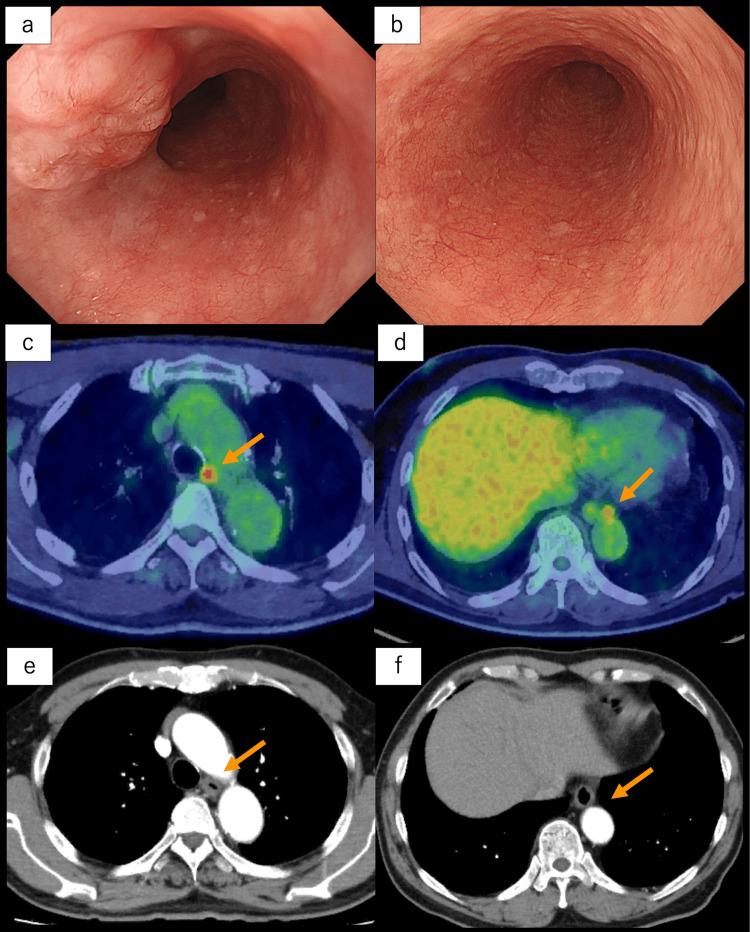

The treatment of multi-organ synchronous neoplasms requires a customized strategy for each case. Here, we present our treatment strategy for synchronous double neoplasms involving thymoma and esophageal cancer, which is a rare occurrence in clinical practice. A 68-year-old man was diagnosed with thymoma and advanced esophageal cancer in the middle thoracic esophagus. Following neoadjuvant chemotherapy for esophageal cancer, a concurrent resection of both lesions was performed using minimally invasive unilateral video-assisted thoracoscopic surgery and laparoscopic surgery with gastric conduit reconstruction via the posterior mediastinal route. The patient was discharged on the 14th postoperative day without any adverse events. Minimally invasive, video-assisted unilateral simultaneous surgery for thymoma and esophageal cancer represents a viable therapeutic approach, offering both curative potential and decreased invasiveness. Furthermore, reconstructing the gastric conduit via the posterior mediastinal route was deemed appropriate, as it may help minimize the risk of invasion of the gastric conduit and radiation exposure in the event of thymoma disease progression. Additionally, we propose a treatment strategy flow for synchronous neoplasms located in adjacent multi-organs. This strategy can be applied to various tumor types and may benefit other complex cases.

多器官同步性肿瘤的治疗需要针对每个病例制定个性化策略。在此,我们展示了针对同时发生的胸腺瘤和食管癌这一临床实践中罕见情况的治疗策略。一名68岁男性被诊断患有胸腺瘤和胸段食管中段的晚期食管癌。在对食管癌进行新辅助化疗后,采用微创单侧电视辅助胸腔镜手术和腹腔镜手术经后纵隔途径重建胃管道,同时切除两个病灶。患者术后第14天出院,无任何不良事件。微创、电视辅助单侧同步手术治疗胸腺瘤和食管癌是一种可行的治疗方法,具有治愈潜力且侵袭性降低。此外,经后纵隔途径重建胃管道被认为是合适的,因为在胸腺瘤疾病进展时,这可能有助于将胃管道受侵犯的风险和辐射暴露降至最低。此外,我们提出了一种针对位于相邻多器官的同步性肿瘤的治疗策略流程。该策略可应用于各种肿瘤类型,可能使其他复杂病例受益。